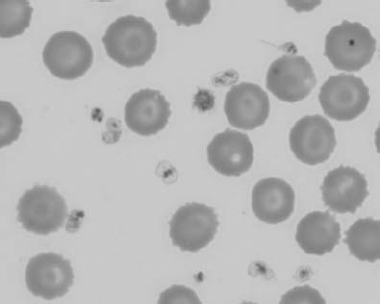

Figure 1.3 Canine blood film showing acanthocytes (also see color section).

Figure 1.10 Canine blood film showing echinocytes I (also see color section).

Figure 1.11 Canine blood film showing echinocytes III (also see color section).